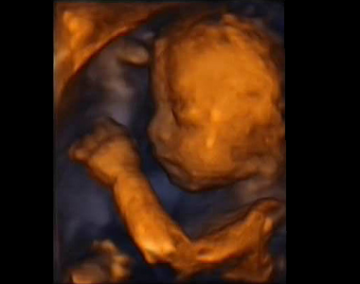

Evasantos - 26. týden

Těhotenské cvičení a vyfocení "kulatícího se" bříška

S kamarádkou jsme také udělaly pár fotek bříška a mně to nedalo a srovnávala jsem je s posledními fotkami z 19. týdne. Břicho se mi teda pořádně "nafouklo" a "zkulatělo".